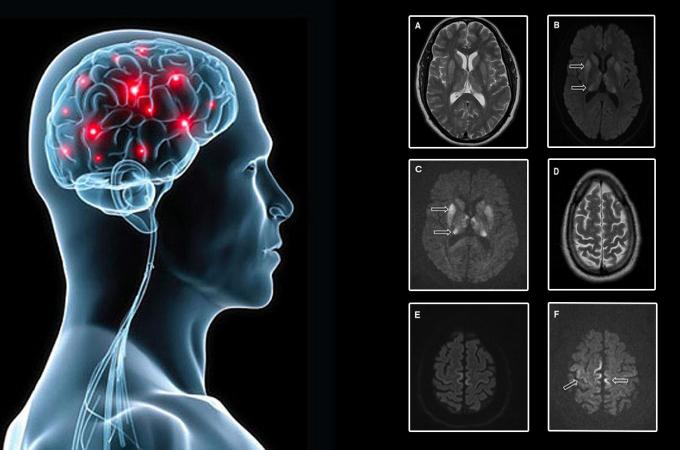

Francie zastavila výzkum prionů poté, co smrtelně onemocněl druhý laborant